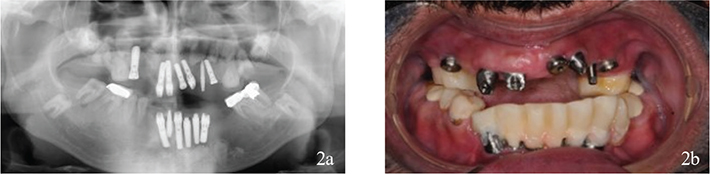

Figure 4

Figure 4. (a, b) Status after treatment.

Six implants in the maxillae and four implants in the mandible (Astra Tech Implant System® Osseospeed® TX, Dentsply Sirona, Mölndal, Sweden) were provided with implant screw-retained fixed partial dentures with metal base and angulated screw channels (Heraeus Dental AB, Biomain®, Helsingborg, Sweden) on Uniabutments (Dentsply Sirona, Mölndal, Sweden). Teeth were restored with fixed dental prosthesis.